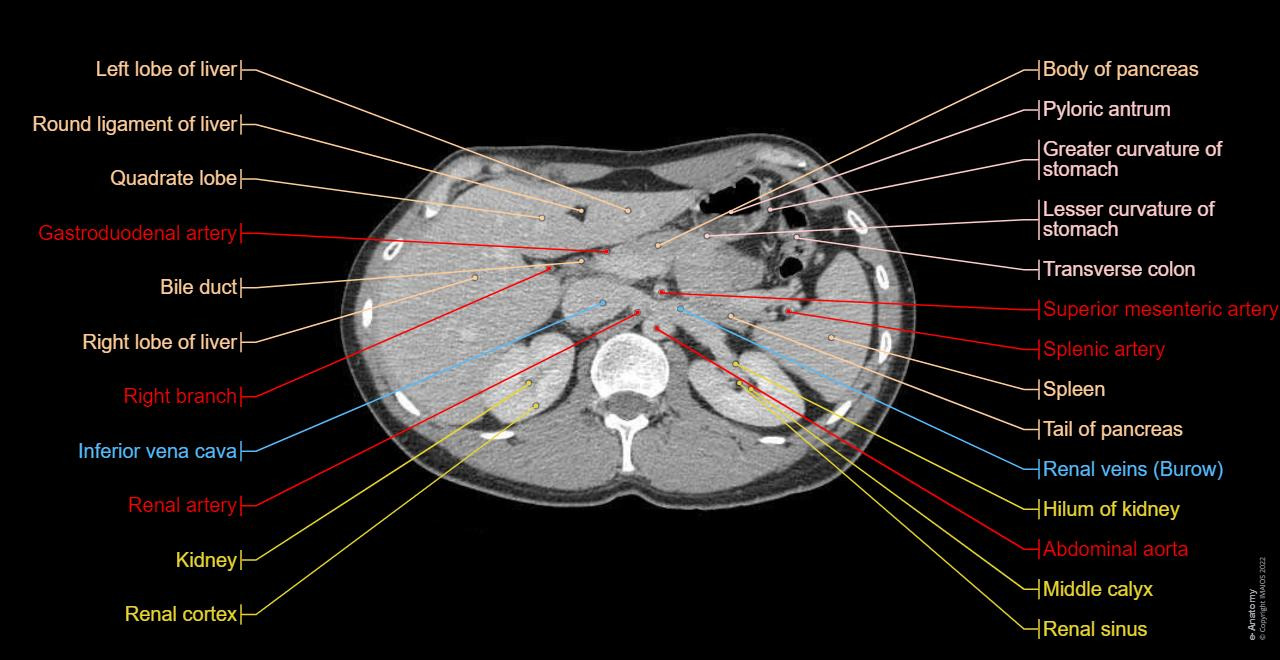

단순 엑스레이나 초음파로는 확인하기 어려운 장기 내부 구조와 병변의 위치, 크기, 성격을 비교적 짧은 시간 안에 확인할 수 있다는 점에서 임상적 활용도가 매우 높습니다. 특히 간, 담낭, 췌장, 신장, 비장, 위장관, 복강 내 혈관과 림프절까지 한 번에 평가할 수 있어 진단 정확도를 높이는 데 핵심적인 역할을 합니다.

복부 CT는 X선을 이용해 인체를 단면 영상으로 촬영하는 검사로, 단순 CT와 조영제를 사용하는 조영 CT로 나뉩니다. 단순 CT는 결석, 출혈, 석회화 병변 확인에 유리하며, 조영 CT는 종양, 염증, 혈관 이상, 장기 손상 여부를 평가하는 데 적합합니다.